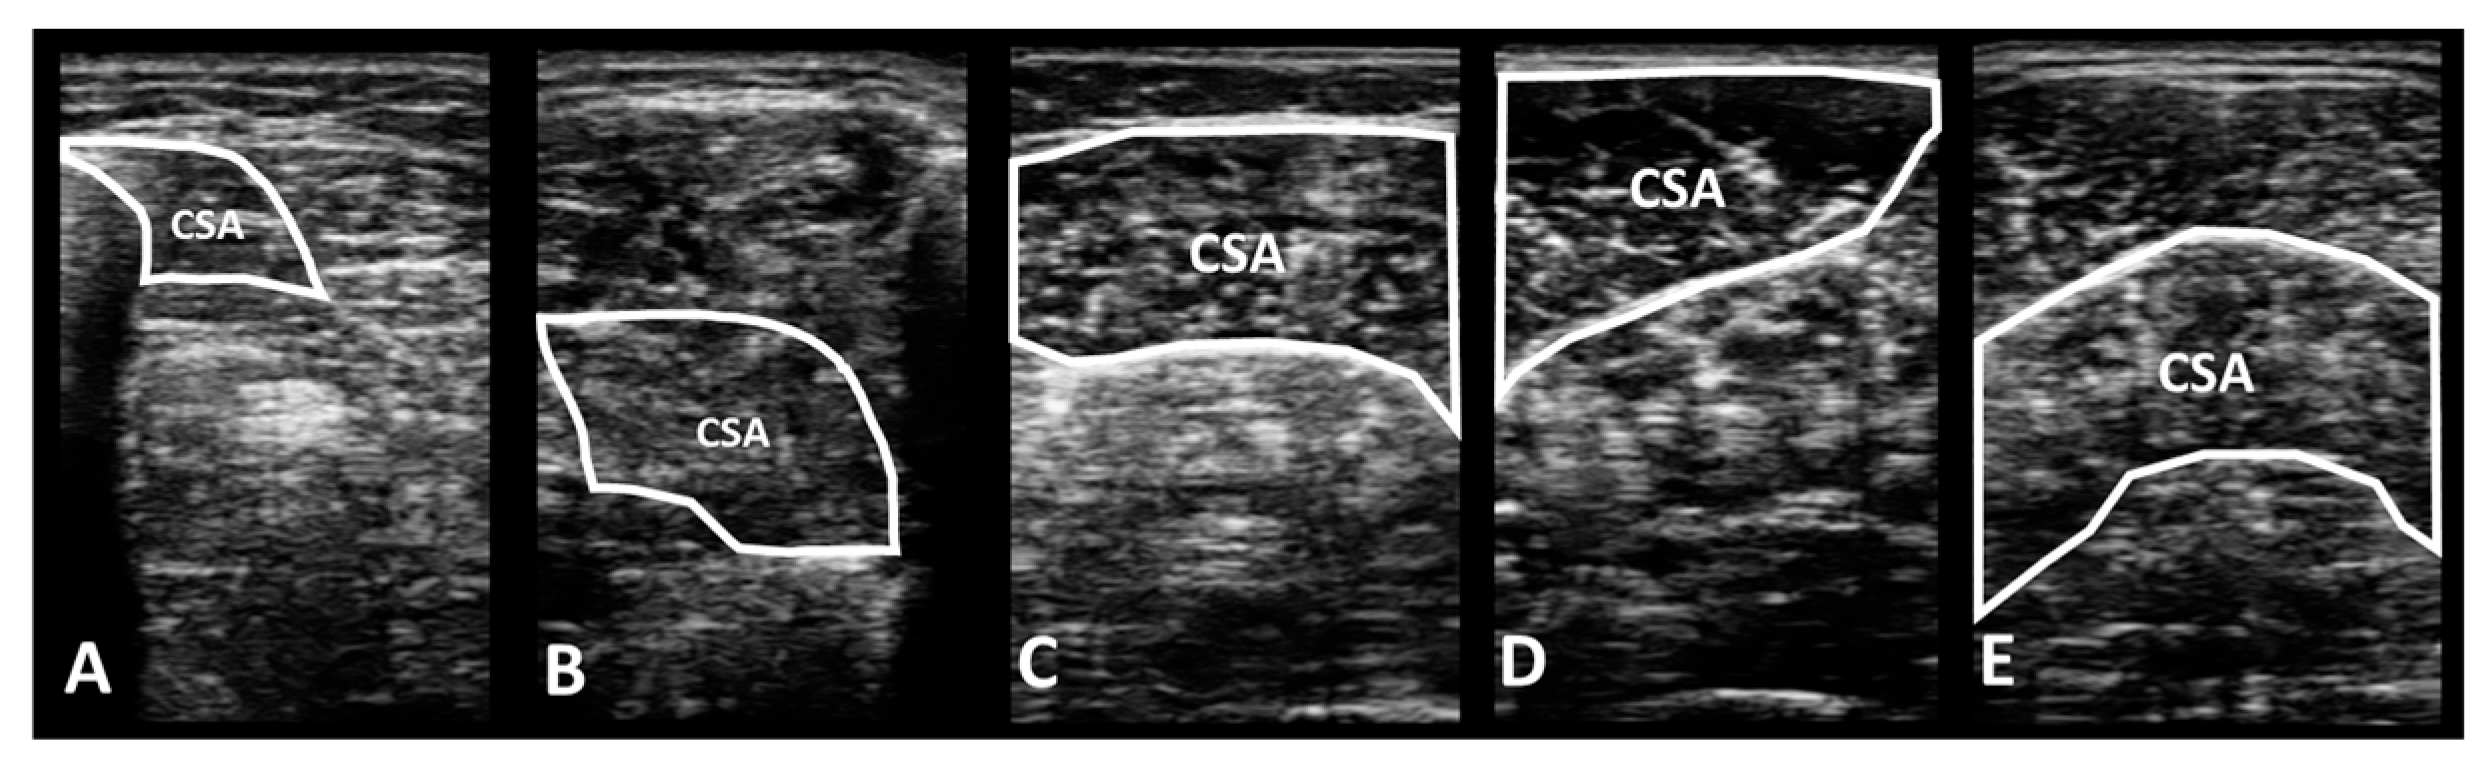

2.4.1. Portable Wireless Diagnostic Ultrasound Device

- Cheon, S.; Chang, E. Inter-rater reliability of a portable ultrasound for the quadriceps and hamstrings thickness measurement in healthy adults. Exerc. Sci. 2020, 29, 71–76. [Google Scholar] [CrossRef]

- Mickle, K.J.; Nester, C.J.; Crofts, G.; Steele, J.R. Reliability of ultrasound to measure morphology of the toe flexor muscles. J. Foot Ankle Res. 2013, 6, 12. [Google Scholar] [CrossRef] [PubMed]

- Crofts, G.; Angin, S.; Mickle, K.J.; Hill, S.; Nester, C. Reliability of ultrasound for measurement of selected foot structures. Gait Posture 2014, 39, 35–39. [Google Scholar] [CrossRef]